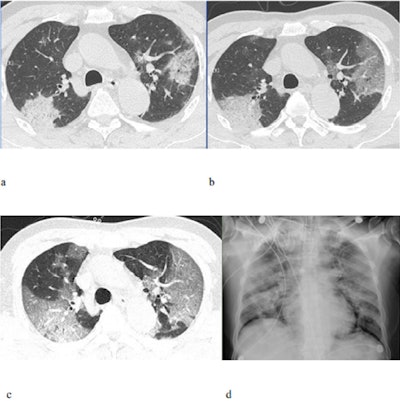

Furthermore, the researchers characterized disease progression for 2019-nCoV by comparing CT features from the first four days of symptom onset to those after the fourth day. Their comparison uncovered a statistically significant increase in the total number of lung findings over time (p = 0.02).

Most prominently, the proportion of ground-glass nodules with consolidation increased from 21% of the lesions in the first four days after symptom onset to 61% after the fourth day (p < 0.001). This statistically significant increase in the percentage of lesions with consolidation was also evident in older patients (50 years or older): 45% of the lesions showed consolidation in the older patients, compared with only 23% in the younger patients (p < 0.001).

This increase in lung consolidation as the disease extended its course indicates that "consolidation lesions could [serve] as a marker of disease progression or more severe disease," Shi and colleagues wrote.